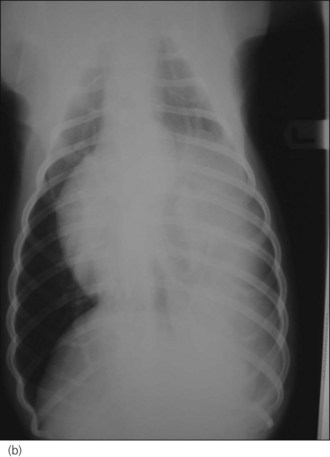

Diagnosis

Radiography is commonly used in animals with suspected diaphragmatic rupture and consistent findings include complete or partial loss of the diaphragmatic line, mediastinal shift, obscuring of the cardiac silhouette, and cranial displacement of abdominal viscera and gas shadows (Figures 28.5 and 28.6). Orthogonal views are recommended but diagnosis may be difficult, for example if displaced viscera are obscured by pleural fluid or in the absence of visceral displacement. Positive contrast gastrography or peritoneography may be required in these cases.

image image

Figure 28.5 (a) Right lateral and (b) dorsoventral thoracic radiographs of a cat showing diaphragmatic rupture.

Figure 28.6 (a) Right lateral and (b) dorsoventral thoracic radiographs of a cross-bred dog showing diaphragmatic rupture.